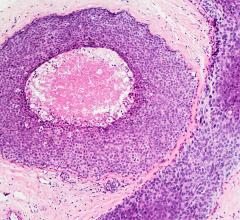

Mammography is a breast imaging technique that uses X-rays to diagnose and locate tumors of the breasts.

Despite decades of progress in breast imaging, one challenge continues to test even the most skilled radiologists ...